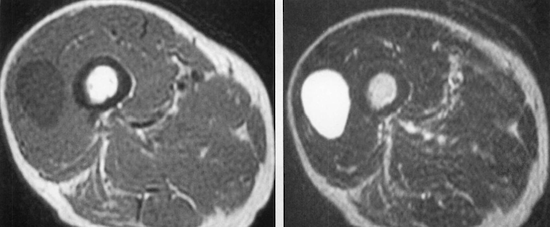

Diagnosis?

Differential?

Intramuscular myxoma - low t1 with peritumoral fat rind, high T2, would have mild internal enhancement. A solitary benign soft-tissue tumor most common in women age 40-70.

Myxoid liposarcoma (look for fatty nodules, fatty septa) and myxoid chondrosarcoma can look very similar!